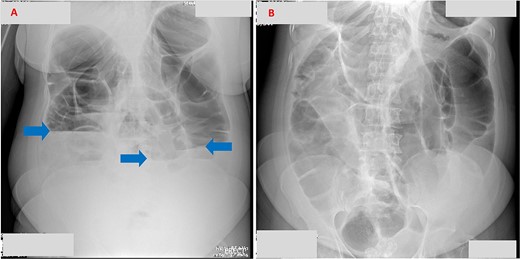

A week later, she presented to the emergency department with signs of complete intestinal obstruction. Blood tests showed a leukocyte count of 5.27 × 109/l, hemoglobin of 13.5 g/dl, and platelets of 329 × 109/L. Serum creatinine, sodium, and potassium were within normal ranges. An abdominal X-ray revealed dilated large bowel loops with multiple short air–fluid levels, consistent with large bowel obstruction (Fig. 1).

(A) Erect abdominal X-ray demonstrating multiple air–fluid levels (arrows). (B) Supine abdominal X-ray showing dilated bowel loops, suggestive of intestinal obstruction.